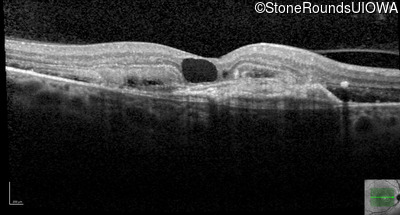

Age at visit: 59 years (Visit 3)